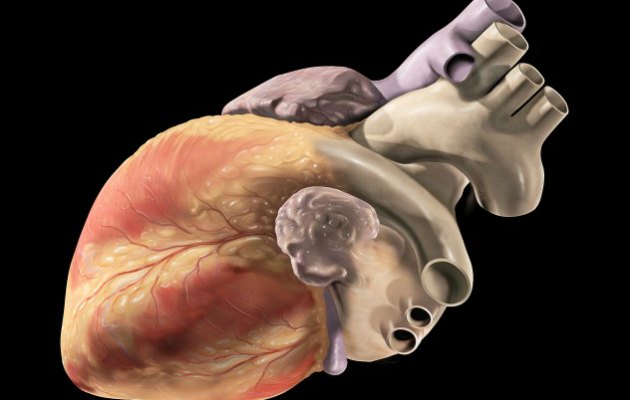

1. Kardiyak MR’ı

Antrasiklin’ler kemoterapinin etkili bir biçimde yürütülmesini sağlıyorlar. Ancak bu tedavi yönteminin uygulandığı çocuklarda ciddi bir yan etkiye sahip olduğu biliniyor. Bu tedaviye maruz kalan çocukların kalpleri zarar görüyor ve ultrasonla görüntülemede çocukların kalplerinin zarar gördüğü kısım bazen yıllar sonra fark edilebiliyor. Bu zamana kadar kap yeteri kadar zarar görmüş oluyor.

Ancak yeni ortaya çıkan bir teknik sayesinde, T1 MRI denilen cihaz sayesinde, çocukların kalplerinin zarar gören çok daha etkili bir biçimde ve hızlıca ortaya çıkarılabilecek. Bu gelişme, çocukların kalp hastalıklarında daha kolay ve hızlı müdahale etmeyi mümkün kılacak.